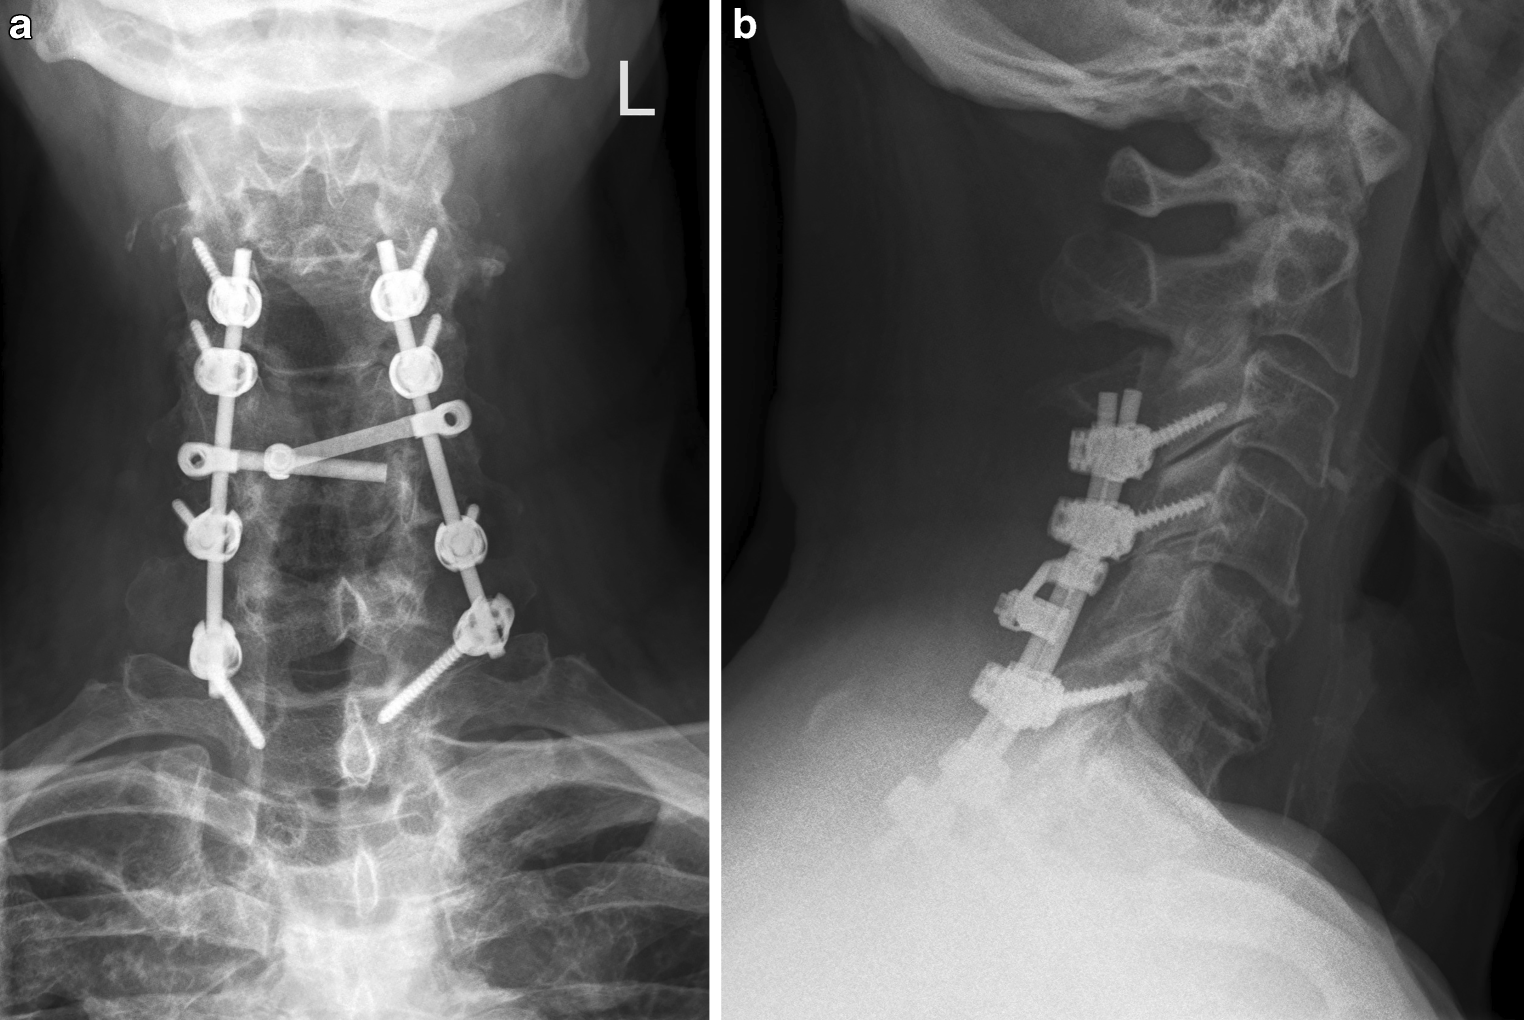

Patiënt B, een 65-jarige man met, behoudens een depressie, een blanco voorgeschiedenis wordt in april 2015 poliklinisch gezien in verband met al twee maanden bestaande progressieve heftige pijn lumbaal en in de linkerheup. De verdere anamnese levert geen bijzonderheden op. Bij onderzoek wordt een pijnlijke, uiterst moeizaam lopende man gezien. Aan hart, longen en abdomen geen afwijkingen. Rectaal toucher is verdacht voor een T4-prostaatcarcinoom. Er is drukpijn over de wervelkolom, met name laagthoracaal en bij het linkerbekken. Oriënterend neurologisch onderzoek is zonder afwijkingen. Laboratoriumonderzoek: Hb 8,6 mmol/l, eGFR 59 kl/1,73m2, PSA 13.500 ng/ml, AF 268 IU/l. Echo prostaat: T4-prostaatcarcinoom. PA prostaatbiopten: Gleason 9 (5 + 4) adenocarcinoom. Skeletscintigrafie met SPECT CT: uitgebreide ossale metastasen, één pathologische lymfeklier parailiacaal rechts, schrompelnier links. MRI wervelkolom/bekken: multipele ossale metastasen met een pathologische inzakkingsfractuur Th12, zonder compressie op het myelum of wortels. Daarnaast uitgebreide metastase linkerfemur met dreigende fractuur.

Conclusie: een patiënt met een cT4N1M1b-adenocarcinoom van de prostaat met een inzakkingsfractuur Th12 zonder neurologische uitval en een dreigende fractuur linkerfemur. Patiënt is direct hormonaal behandeld. Vervolgens is hij door de orthopeed geopereerd waarbij in één zitting een vertebroplastiek Th 12 is verricht en een verlengde gamma nail links is ingebracht (fig. 2). Patiënt is goed hersteld van de operatie. Het verdere beloop is op hoofdlijnen samengevat als volgt:

Figuur 2

Patiënt B: Dorsale (a) en laterale (b) röntgenfoto van de vertebroplastiek van het pathologische inzakkingsfractuur van Th12. De (preventieve) verlengde gamma nail in verband met het dreigende femurfractuur (c)